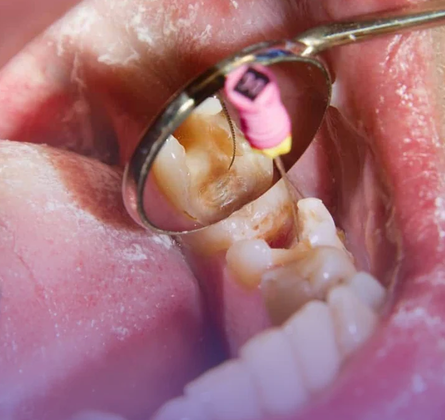

El procedimiento se realiza bajo anestesia local y se lleva a cabo en varias fases. Primero, el odontólogo o endodoncista accede a la cámara pulpar del diente para extraer la pulpa dañada. Luego, se limpian y desinfectan cuidadosamente los conductos radiculares con instrumentos especializados y soluciones antimicrobianas. Posteriormente, estos conductos se rellenan con un material biocompatible, generalmente gutapercha, que sella el interior del diente. Finalmente, se coloca una restauración temporal o definitiva, como una corona, para proteger el diente y devolverle su forma y función.